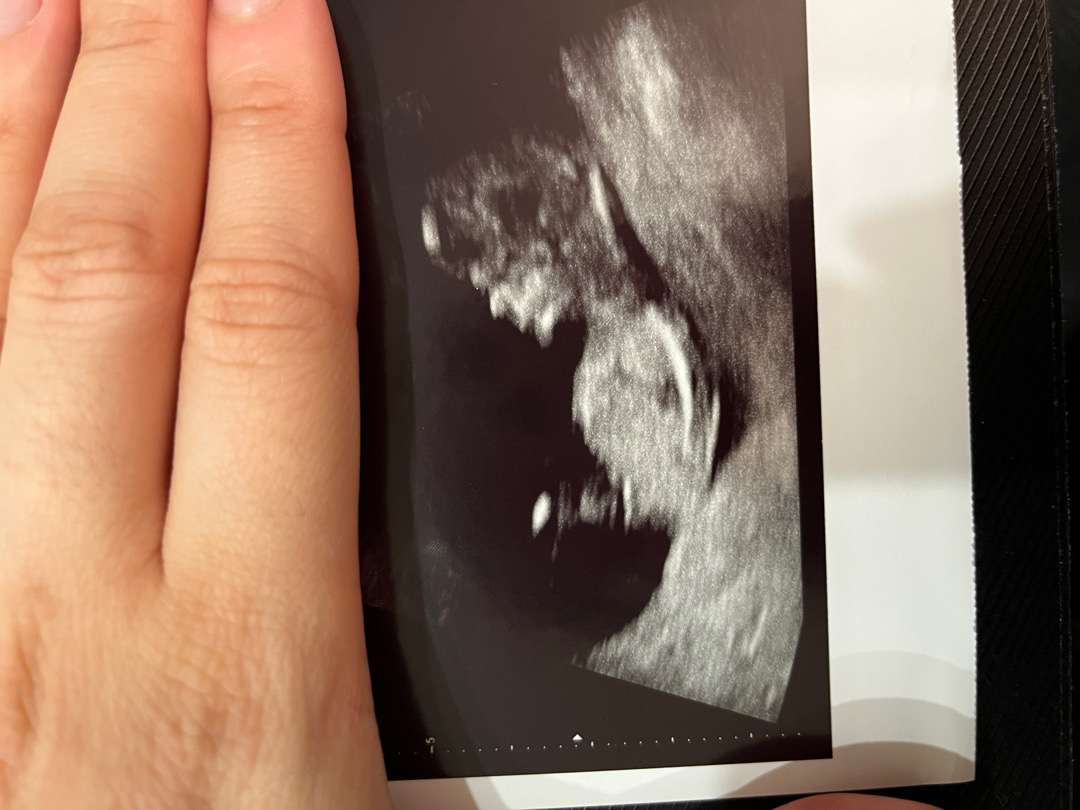

오늘 1차 기형아 검사 하구 왓어요!! 초음파 보는데 방방뛰는 아가 보면서 너무 귀여워서 웃음 참느라 혼났네요ㅠㅜㅎㅎㅎ 느낌상 아들같은데 혹시 사진으로도 보이는지 궁금하네요!!!